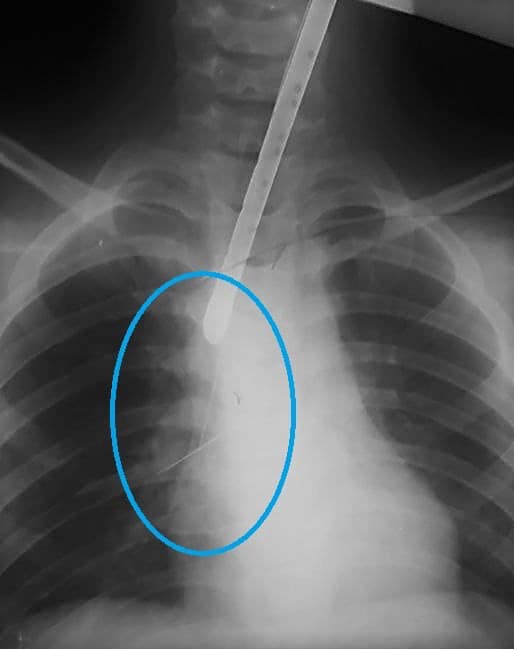

У Дніпрі в лікарню потрапила дитина із булавкою в дихальних шляхах. Зокрема, шпилька встигла підколотися до трахеї, що ускладнило її вилучення.

Так, дитина проковтнула шпильку, і під час діагностичного ендоскопічного дослідження виявилося, що вона підкололася до трахеї.

Зокрема, діставали сторонній предмет ціла бригада медиків. Спочатку вони намагалися її дістати за допомогою "петлі", але шпилька почала "мігрувати" вниз дихальними шляхами. Там до правого бронха вона підкололася до сегментарної бронхи й через необережний рух могла стати причиною ускладнень.

Медики без операції дістали з бронхів дитини булавку (facebook.com/odkl.org)

Тому після певних обережних та повільних маніпуляцій їм вдалося видалити злощасну шпильку з дихальних шляхів маленького пацієнта та майже не травмуючи слизову ані бронха, ані трахеї.